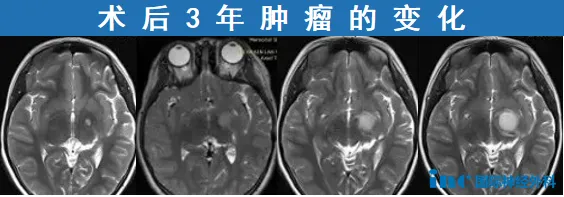

这个案例出自INC福洛里希教授发表的学术论文《Interhemispheric Tr...